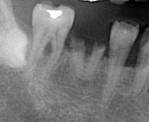

症例2

右下 6 番単独欠損ですが、中等度歯周病(水平的骨吸収あり)のため、ブリッジでの治療ですと隣接歯の寿命を極端に縮めてしまう可能性があります。